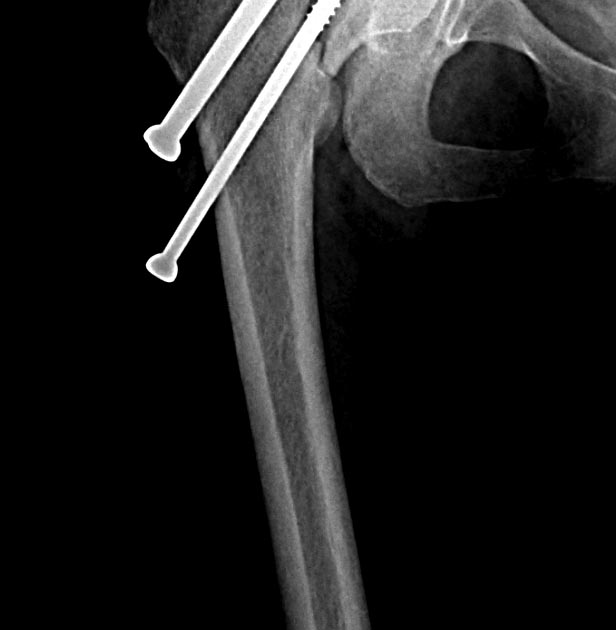

Две несросшихся шейки бедра, пацинтка 27 лет, травме 5 месяцев

БИОС плеча, Чкдо на л/запястный сустав, Биос левого бедра, Мос правой шейки бедра винтами.

Причина обращения -выявленный ложный сустав шейки левого бедра. При дообследовании выявлен несросшийся перелом шейки бедра на винтах.

Опороспособность обеих н/конечностей резко снижена, может стоять на правой, передвигается на каляске.Что думаем: слева однозначно протез, но бедро не срослось, менять гвоздь на пластину, пластина или которкая, или опасность конфликта с ножкой протеза, можно подождать консолидации и разбираться с правой конечностью.Справа остесинтез с коррегирующей остеотомией, но смущает состояние верхнего полюса после миграции винтов, что может повлечь протезирование на фоне нарушения анатомии проксимального бедра, что не хорошо для выживаемости протеза у 27 летней пациентки. Может сразу протез ?КТ головки не информативна из-за винтов